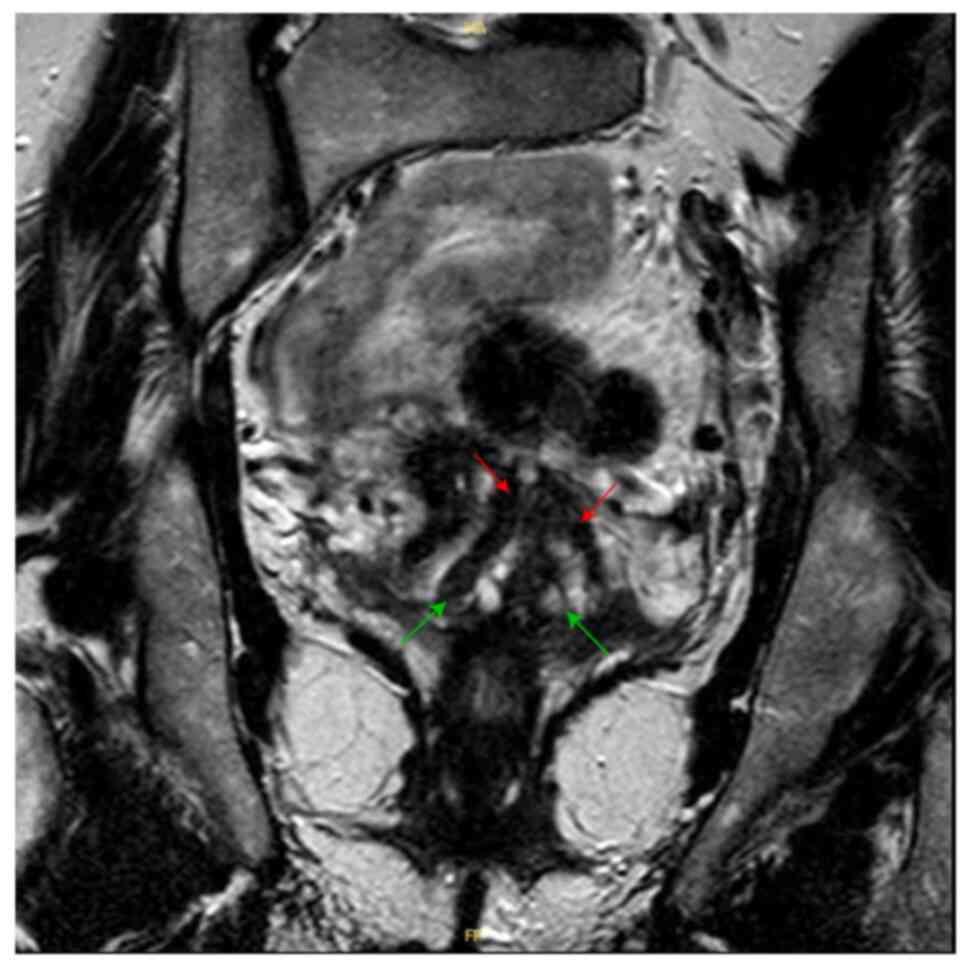

The patient is a female born to non-consanguineous parents. Her clinical presentation comprises features of VACTERL/HFGS syndrome including bicornuate uterus (double uterine cavities, double cervix), left arm agenesis, scoliosis, and BAV (Figs. 1 and 2). The patient was delivered at term with an upper left arm agenesis. Any imperforate anus nor anal atresia or tracheoesophageal fistula were noted in the patient's birth.

Figure 1.

Pelvic magnetic resonance imaging of the patient at 40 years old: Axial T1 weighted sequences showing double uterine cavities (red arrows) with double cervix (green arrows).

Pelvic MRI showed two uterine cavities and a double cervix. On the T1-weighted sequence, there is no hematic retention in the right or left side of the uterine horns. No anomalies in the junction zones or the myometrium. Both appendages are of normal size and regular outline (Fig. 1). Of note, the patient did not have frequent pelvic pain or miscarriage history due to her bicornuate uterus.